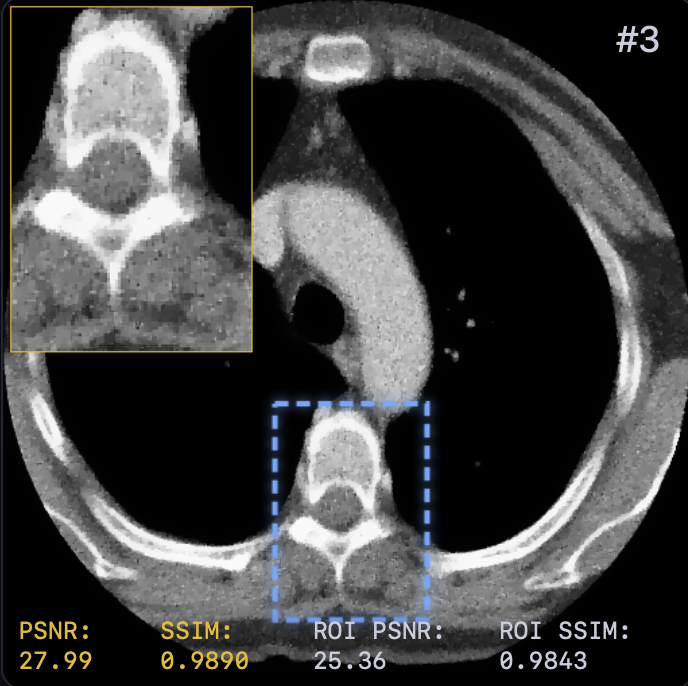

The reconstruction results are shown in Fig. 2. A zoomed-in region was extracted for a closer look with both PSNR and SSIM values attached. LTV preserves fine structures, such as vessel continuity, and reduces streak artifacts—critical for diagnostics—while avoiding the over-smoothing of TV or the anatomical inconsistencies of FBP+U-Net.